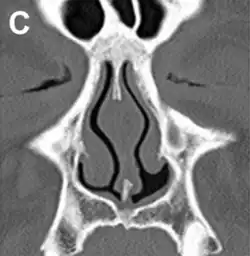

ENS caused by loss of the inferior half of the left inferior turbinate.